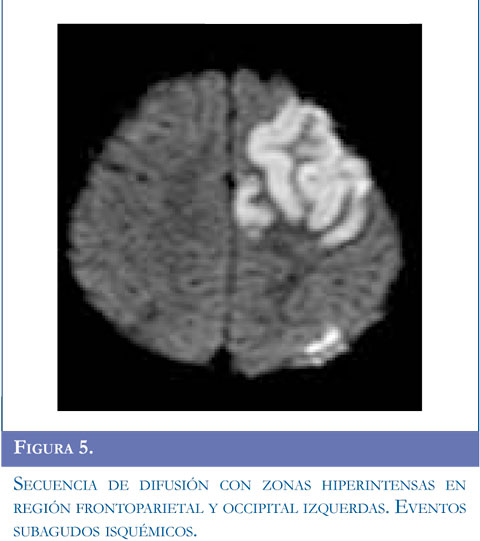

Se inició manejo con carbamazepina, se solicitó RM simple reportada con lesión sugestiva de tipo desmielinizante que compromete sustancia blanca y centros semiovales, sin realce al contraste. Ante la recurrencia de evento de hemiparesia contralateral se realizó RM de control que mostró aumento en el número de las lesiones. Se estudió enfermedad neu-rometabólica con compromiso de sustancia blanca con normalidad en ácidos orgánicos, aminoácidos en orina, acido láctico, ácidos grasos de cadena larga. Presentó nuevo evento de hemiparesia izquierda con estatus convulsivo focal se realizó TAC de cráneo que mostró ACV isquémico parietooccipital derecho, se solicitó panangiografía y doppler carotídeo. Angiografía con compromiso bilateral con hallazgos sugestivos de enfermedad de Moyamoya, y doppler trascraneal hallazgos compatibles con hipoplasia proximal de arterias cerebrales media y anterior izquierda compensado con flujo colateral a través de comunicante posterior izquierda. Valorado por neurocirugía no consideraron manejo quirúrgico. El paciente ha continuado presentando episodios transitorios de ACV. Figuras 4, 5 y 6